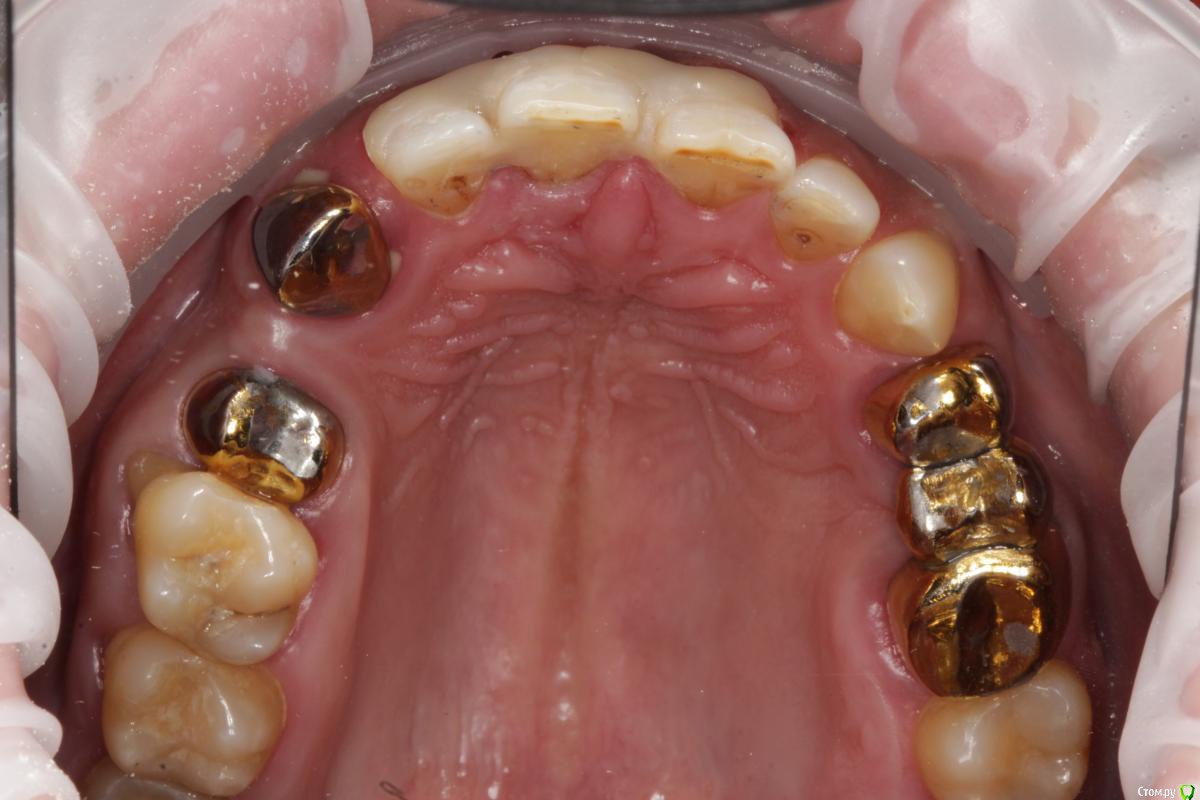

Витторио Орлионе Опубликовано 4 июля, 2018 Поделиться Опубликовано 4 июля, 2018 очень прошу мудрого совета у вас дорогие коллеги!!! Пациента беспокоят выделения из под десны, при осмотре выявлен карман глубиной 5 мм, зуб витален и стратегически нужен для дальнейшего лечения, потому что пациент хотел бы реабилитировать верхнюю челюсть, причиной всего этого как мне кажется стал нависающий край коронки, можно ли добиться стабилизации процесса сняв коронку проведя глубокий скейлинг, чтобы в будущем взять этот зубик под опору в мостовидном протезе или лучше на него все таки не расчитывать и удалить... Ссылка на комментарий

Карен Аванесов Опубликовано 4 июля, 2018 Поделиться Опубликовано 4 июля, 2018 Судя по фото проблемы с пародонтом имеют генерализованный характер, решать надо глобально. Ссылка на комментарий

Витторио Орлионе Опубликовано 4 июля, 2018 Автор Поделиться Опубликовано 4 июля, 2018 Судя по фото проблемы с пародонтом имеют генерализованный характер, решать надо глобально.уже удалён зуб 1.1 и планируется удаление зуба 1.6 (феномен Попова-Годона), а далее мостовидный протез 1.7 - 1.5 - 1.3, 1.2-2.1, 2.4 - 2.6, одиночные коронки 2.2, 2.3. А как бы поступили вы? Ссылка на комментарий

Corsag21 Опубликовано 5 июля, 2018 Поделиться Опубликовано 5 июля, 2018 (изменено) Штампанину на мороз бы выгнал для начала.Определил состояние пародонта: глубина карманов, зубодесневое прикрепление, etc...Ну и оттуда работать Что делать когда мы узнаем глубину карманов, зубодесневого прикрепления? По снимку ОПТГ видно что примерно 50% костной ткани есть и во рту нет оголения корней. Если зубы устойчивы, то можно несъемные делать. Хуже когда все зубы подвижны 1 степени и соматическое заболевание, я не знаю оптимального способа протезирования на эти случаи. Что-то мне кажется что у пациента сахарный диабет. Почему удаляете 1.6 - он неустойчив или периапикальная патология? Изменено 5 июля, 2018 пользователем Corsag21 Ссылка на комментарий